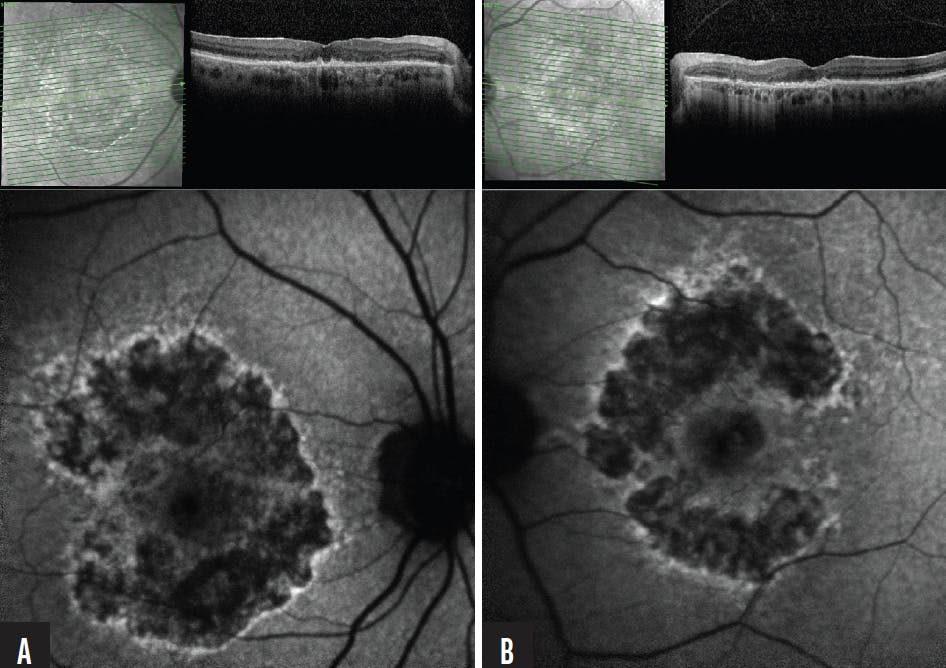

The patient returned in 5 months with complaints of significant visual decline. Her BCVA was 20/40 OD and 20/30 OD, and foveal involvement as seen on FAF was present OU (Figure 3). By this point, both avacincaptad pegol and pegcetacoplan were approved for the treatment of GA, and I initiated a discussion about treatment options with the patient and her daughter, who had provided transportation to the clinic for past appointments. They decided that burden of care (ie, monthly or every-other-month treatment, risk of infection) was higher than the proposed outcome (ie, potential arrested development of GA lesions), and declined to start therapy. I asked the patient to return in 3 months.

Figure 3. The patient returned to the clinic 5 months after the previous appointment, 1 month earlier than requested. She reported visual decline OS, and her BCVA had decreased from 20/25 OS to 20/30 OS (B). FAF imaging showed that foveal involvement was present OU, and that increased hypertransmission could be observed on OCT on OS as well as OD (A)

The patient and her daughter returned in 6 months. The patient’s vision, although not any different than her last appointment as measured via BCVA, had worsened to the point that she could no longer safely drive (Figure 4). The patient requested treatment, and a plan was put in place to begin a therapeutic regimen.

Figure 4. The patient returned 6 months after her previous appointment; at this point, nearly 3 years had elapsed since her initial presentation. Her BCVA was stable at 20/40 OD (A) and 20/30 OS (B), but the patient’s ability to drive had deteriorated. She opted for anti-complement therapy.